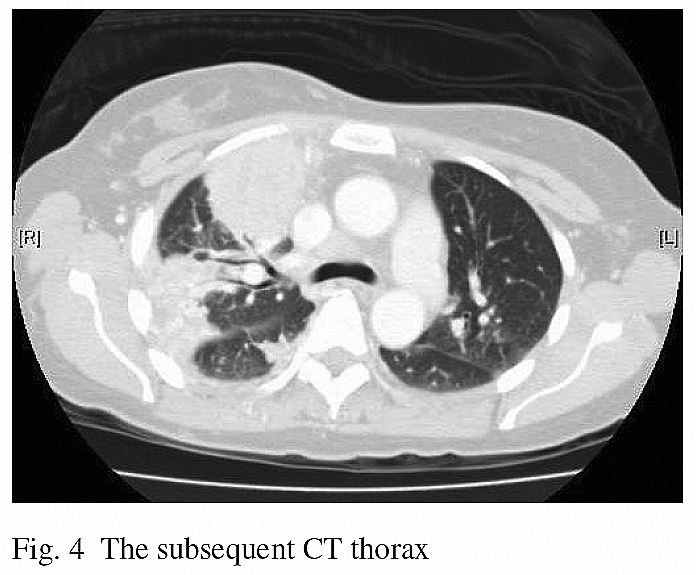

Due to the persistent right upper lobe consolidation, bronchoscopy was performed. The tracheobronchial tree was normal and the transbronchial biopsy (from right upper lobe), bronchial aspirates for culture, acid-fast stain and cytology were all negative. Since the subsequent follow-up CXRs showed worsening of her right upper lobe infiltrate, another CT was repeated and revealed worsening right upper lobe consolidation that involved all three segments of right upper lobe. (Fig. 4)